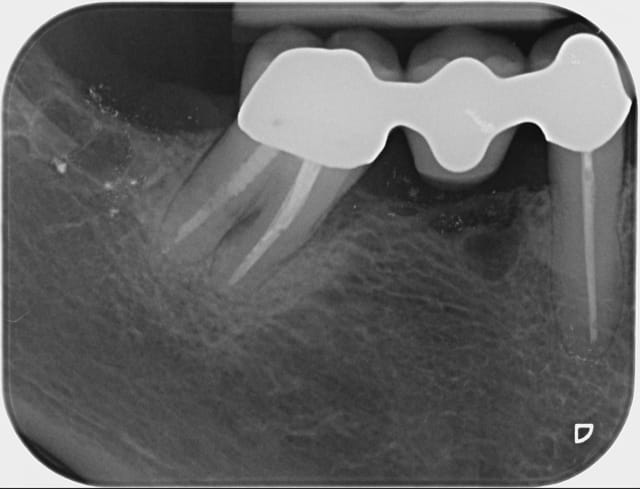

Mon hypothèse est que cela c'est joué pendant la période de temporisation. Je ne pense pas à un problème occlusal du provisoire. A la vue de tes radio, il semble voir un sinus lift avec pose implant dans un second temps, ce qui nous donne minimum 6-8 mois sous provisoire (sans compter l’éventuelle période avant le sinus lift). L'égression "orthodontique" serait alors du à la façon dont ta patiente a (dys)fonctionné. En ayant un contact trop prononcé sur les antérieures (et donc désocclusion en post), par un mouvement de bascule, on obtiendrait une égression de la prémo. Le jour de la pose des définitives, tout va bien. Seulement la prémo n'ayant pas de "contention", récidive. Les points de contact un peu fort limiterai l'égression "physiologique".

??? Supraclusion c'est recouvrement dentaire excessif, quasi toujours incisif. Même avec un recouvrement incisif normal, avec ce bridge pro bien réalisé de 15 à ... (ant? secteur 2?), une position mandibulaire plus avancée ou en latéralité gauche suffirait à créer une force d'égression sur la prémo.

Par contre il manque grave du décalage latéral immédiat surtout a gauche, a cela on rajoute une supra clusion du bloc ant.

Je la vois comme ca l histoire :

elle est bloquée en latéral a gauche . Pour se décontracter ,elle essaye de partir devant.elle ne peut pas non plus. Elle déporte a fond a droite et en arrière pour se caler sur la 45+46, comme par hasard elle a perdu la 46 ?bientot elle va perdre les 2 centrales en egressant et en partant en eventail,

quand elle se cale elle est capable de se mettre en occlusion croisée coté droit,et si ce que je te dis est vrai tu vas avoir une fracture de ceram eu haut a droite.....

A mon avis tu as augmenté la dvo et tu as bien fait mais + tu augmentes la dvo + il faut donner de la laxité latérale posterieure,